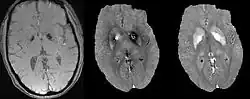

A unique advantage of MRI is that it provides not only the phase image but also the magnitude image. In principle, the contrast change, or equivalently the edge, on a magnitude image arises from the underlying change of tissue type, which is the same cause for the change of susceptibility. This observation is translated into mathematics in MEDI,[13] where edges in a QSM which do not exist in the corresponding magnitude image are sparsified by solving a weighted norm minimization problem.[14]

MEDI has also been validated extensively in phantom, in vitro and ex vivo experiments. In an in vivo human brain, MEDI calculated QSM showed similar results compared to COSMOS without statistically significant difference.[15] MEDI only requires a single angle acquisition, so it is a more practical solution to QSM.